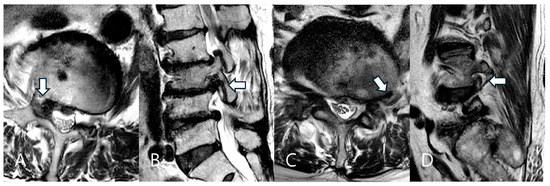

4.3. Foraminal vs. Extraforaminal LDH: Impact on Surgical Complexity

- Ahn, Y.; Yoo, B.R.; Jung, J.M. The irony of the transforaminal approach: A comparative cohort study of transforaminal endoscopic lumbar discectomy for foraminal versus paramedian lumbar disc herniation. Medicine 2021, 100, e27412. [Google Scholar] [CrossRef] [PubMed]

| LDH Zone | Foraminal | 53 | 70.7% |

| Extraforaminal | 22 | 29.3% | |